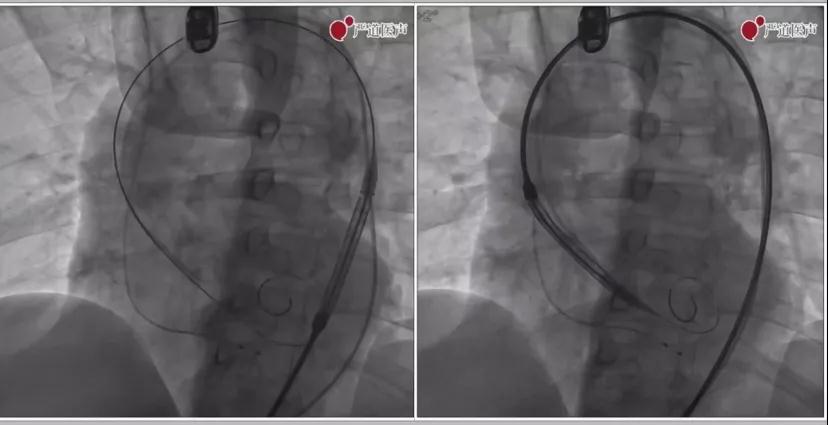

右股动脉穿刺、植入导丝:4F微穿刺右股动脉,确认穿刺点位于股动脉血管中心位置,交换为6F鞘管,2把Proglide缝合器预埋后,11F鞘管扩张股动脉穿刺点后,置入20F大鞘。通过6F AL1导管和直头导丝跨主动脉瓣送入左心室。交换为猪尾导管,全麻下跨瓣峰值压差50mmHg。Lunderquest超硬钢丝,头端塑形后送入左心室,导丝位置更深一些支撑力更好,完全到心尖部最佳。

通过病变瓣膜

加硬钢丝塑形

加硬钢丝植入心腔